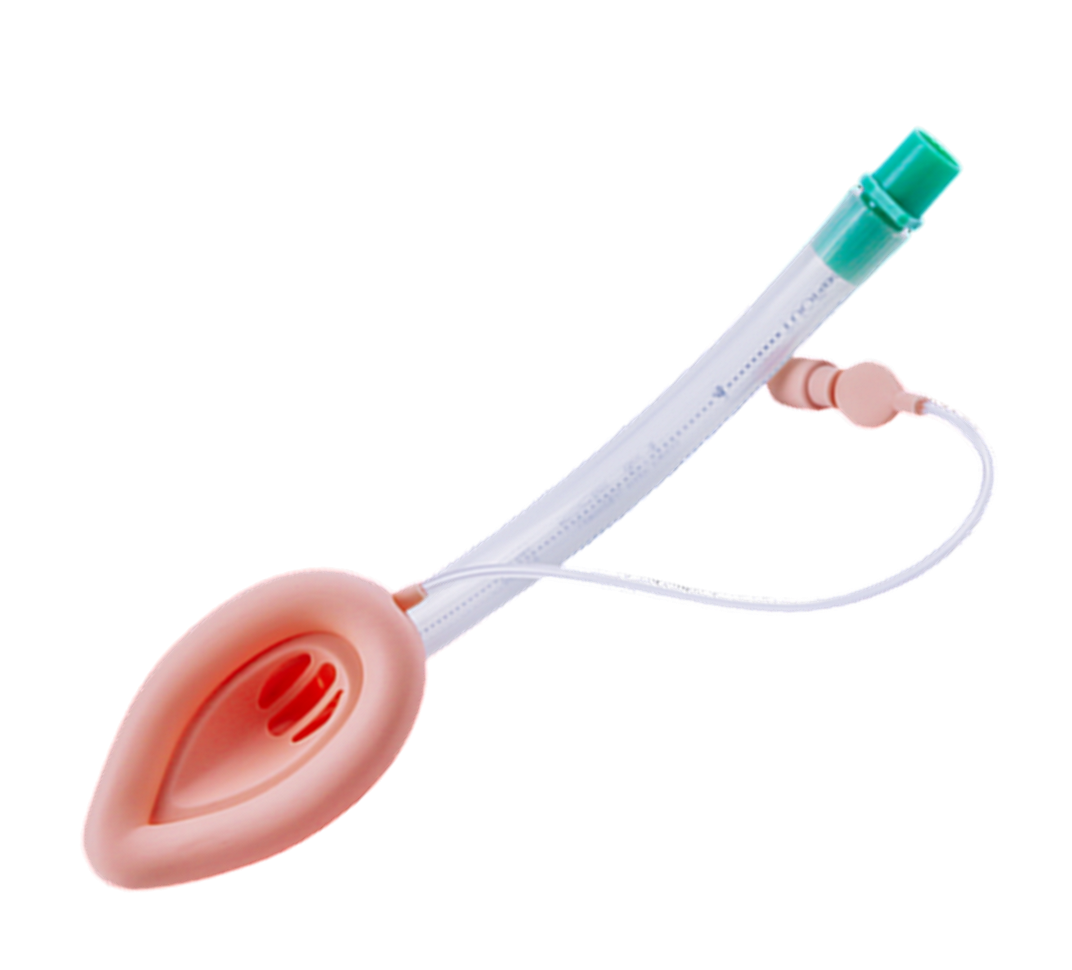

食道引流型喉罩

一次性醫(yī)用喉罩(普通型)